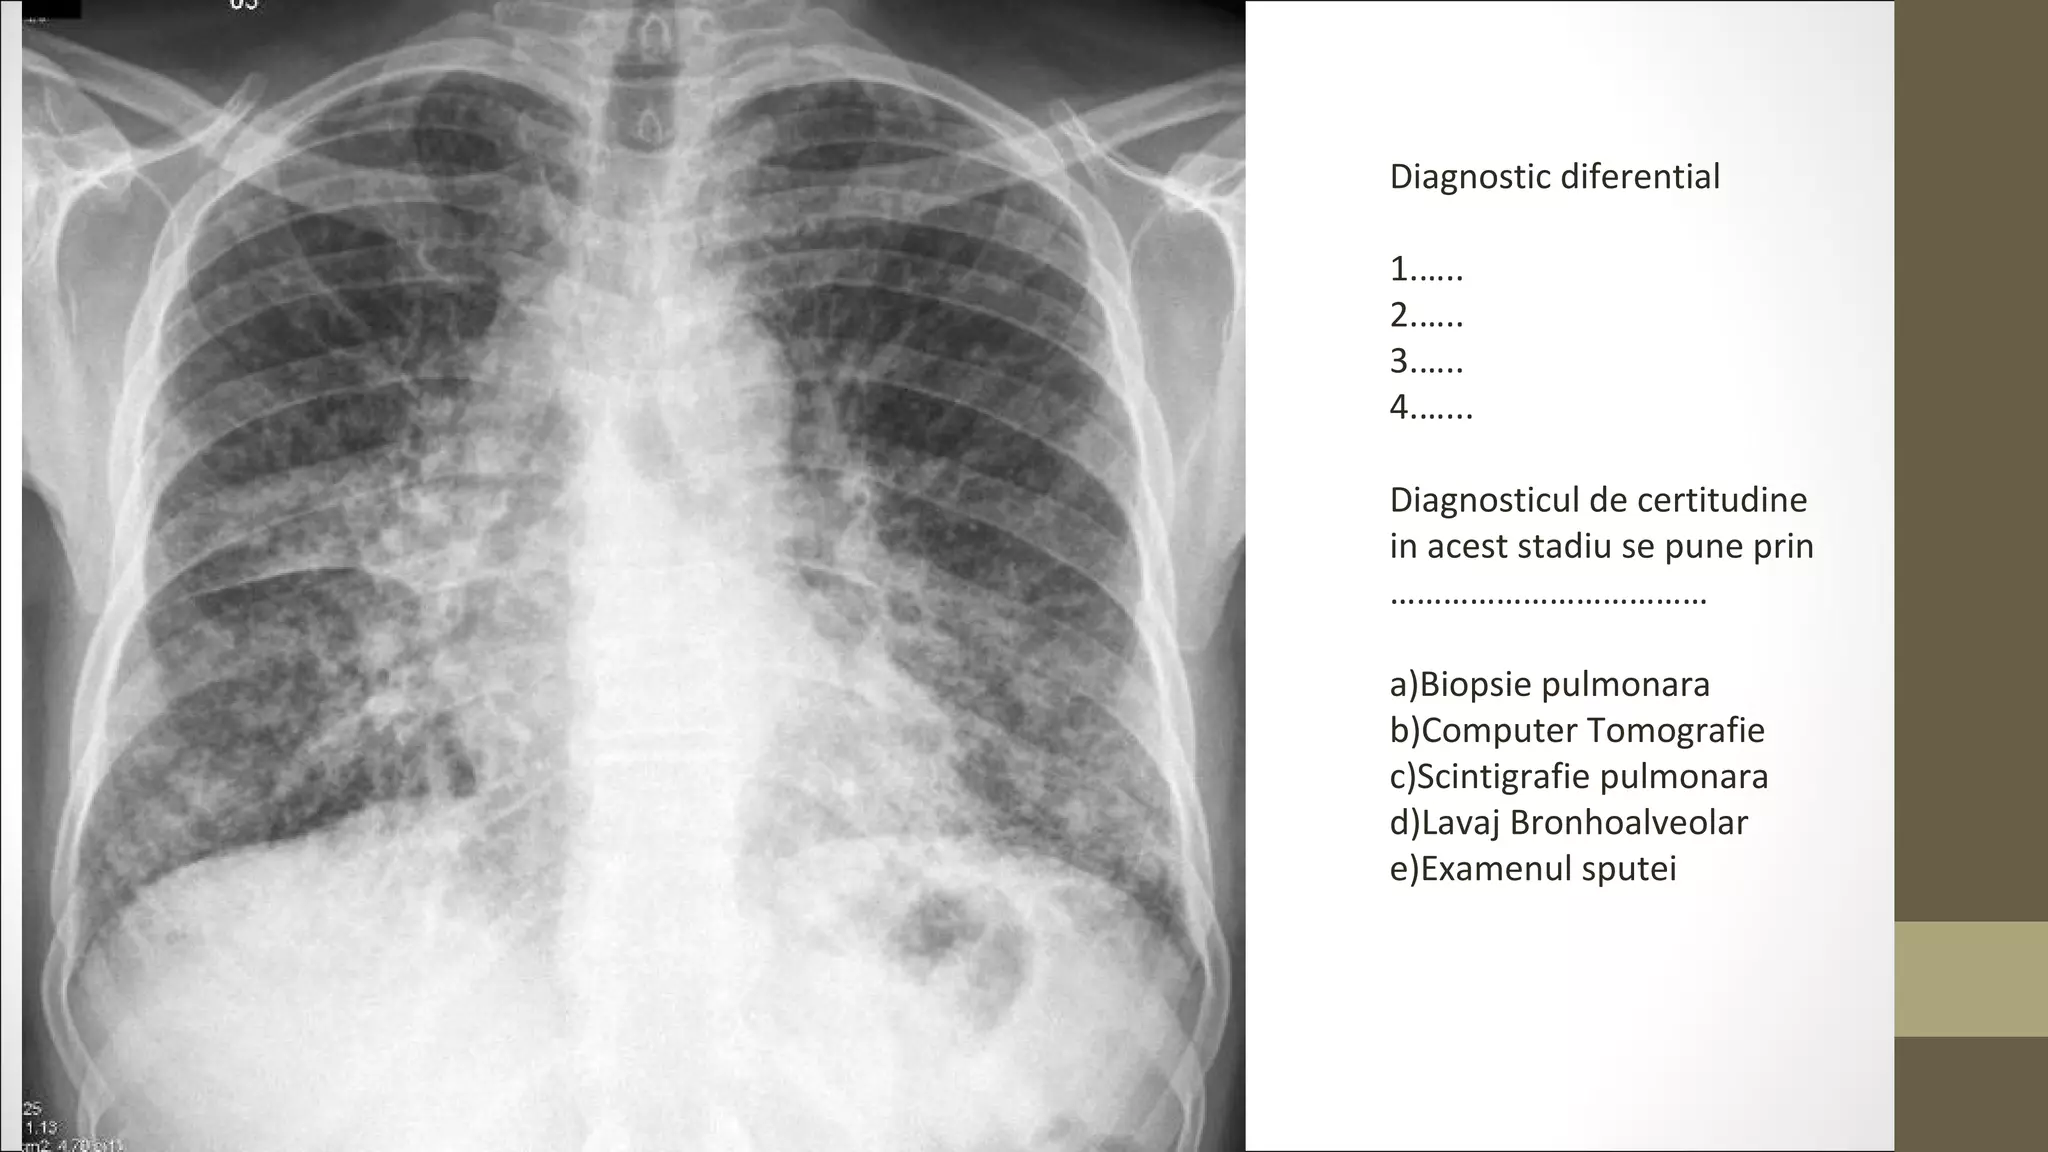

Diagnostic diferential

1.…..

2.…..

3.…..

4.…...

Diagnosticul de certitudine

in acest stadiu se pune prin

………………………………

a)Biopsie pulmonara

b)Computer Tomografie

c)Scintigrafie pulmonara

d)Lavaj Bronhoalveolar

e)Examenul sputei

Diagnostic diferential 1.….. 2.….. 3.….. 4.…... Diagnosticul decertitudine in acest stadiu se pune prin ……………………………… a)Biopsie pulmonara b)Computer Tomografie c)Scintigrafie pulmonara d)Lavaj Bronhoalveolar e)Examenul sputei